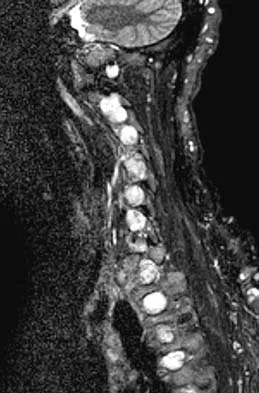

A 60-year-old woman with a history of breast cancer has progressive paraparesis. The MRI scan is shown in Figure 28. What form of management is most likely to restore or maintain ambulation?

Explanation

Surgical decompression and stabilization have been shown to be the most effective means of improving neurologic function. Decompression is most reliably done from the side of the compression, which is anterior in this patient. Harrington KD: Metastatic tumors of the spine: Diagnosis and treatment. J Am Acad Orthop Surg 1993;1:76-86.